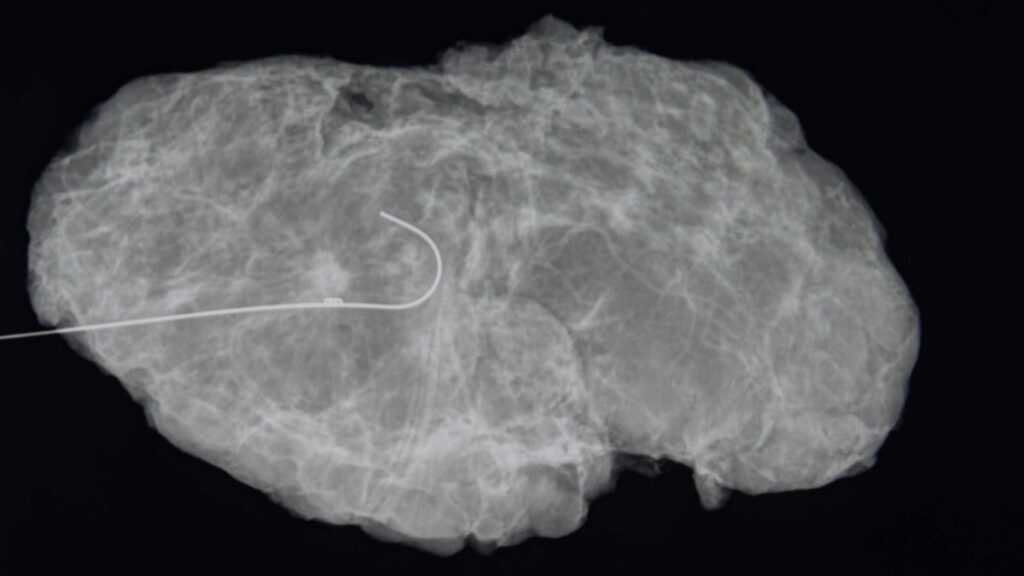

Los investigadores querían saber: ¿Este dogma seguía siendo cierto? Siguieron a casi 200 mujeres con dos o tres tumores en un seno que se sometieron a lumpectomías seguidas de radiación. Las pacientes tenían entre 40 y 87 años de edad.

Para participar en el estudio, sus tumores tenían que tener menos de 5 centímetros y estar separados por 2 a 3 centímetros de tejido mamario normal. Después de cinco años, solo el 3% vio que el cáncer regresaba, tasas similares a las de estudios previos de lumpectomía en pacientes con un solo tumor.

Eso habría arrojado mejores datos, pero sería casi imposible encontrar mujeres dispuestas a ser asignadas al azar, dijo Boughey, lo que hace que ese experimento no sea práctico. En el estudio, las mujeres que se sometieron a una resonancia magnética antes de la cirugía obtuvieron los mejores resultados, lo que sugiere que las exploraciones por resonancia magnética pueden ayudar a los cirujanos a ser más minuciosos en la extirpación del cáncer.